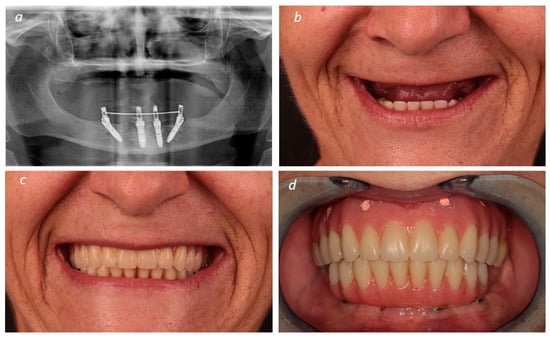

Description of the Technique

3. Results